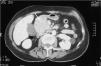

Se realizó una ecografía abdominal en la que se visualizaba una masa en la cabeza pancreática que parecía infiltrar el duodeno, con dilatación de la vía biliar extra e intrahepática. Se solicitó serología para virus hepatotropos, que resultó negativa, y para el VIH, que fue positiva. En la TAC abdominal (fig. 4) se confirmó la existencia de una gran masa pancreática de 6 por 7 cm de diámetro, así como dilatación de la vía biliar y del conducto de Wirsung con probable infiltración por contigüidad de la vena mesentérica superior, además de pequeñas adenopatías retroperitoneales y portocavas. Ante el tamaño y la heterogeneidad de la lesión, y dado el antecedente de infección por el VIH, se realizó punción con aguja fina de la masa, que resultó indicativa de LNH. Con el diagnóstico de infección por el VIH en estadio C3 (carga viral de 225.000 copias VIH-1; log5: 32; células CD4: 136) y LNH pancreático de estirpe B CD 19+ (fenotipo: CD20bright, CD%, CD23, FMC7+, CD10+, CD38+, CD11c, CD103, Cd30, Ki67 con débil clonalidad kappa), se realizó estudio de extensión con biopsia de médula ósea (figs. 5 y 6), punción lumbar y TAC cervicotorácica que confirmaron infiltración tanto de sistema nervioso central como de la médula ósea, sin encontrar afectación en otros órganos. Se comenzó tratamiento con CHOP, quimioterapia intratecal y profilaxis para la infección por Pneumocistis con TMP-SMX. La paciente presentó un cuadro de hemorragia digestiva alta con inestabilidad hemodinámica y anemización que requirió la transfusión de 5 concentrados de hematíes. Se realizó gastroscopia urgente sin detectar el lugar de la hemorragia, y únicamente se observaron restos hemáticos en el estómago, que era normal. El cuadro cedió con tratamiento médico. La paciente se encuentra estable en el momento actual, pendiente de completar el último ciclo de quimioterapia intratecal, con mejoría clínica y analítica, y desaparición de la ictericia.

Fig. 4. TAC abdominal: masa pancreática de 6 x 7 cm que parece infiltrar duodeno.